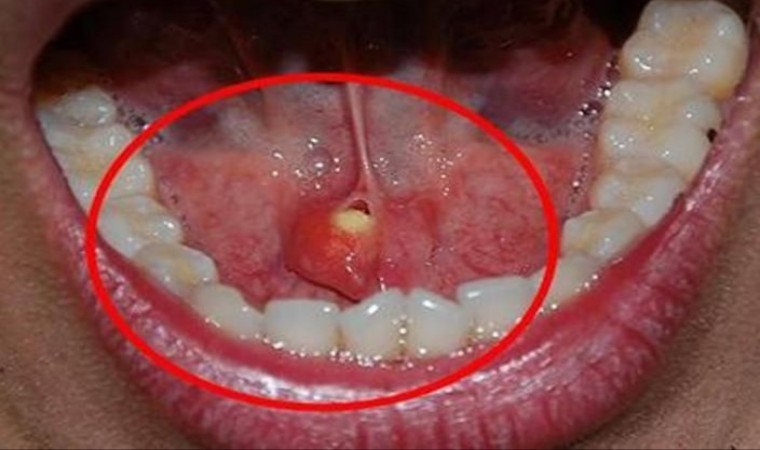

Tükürük bezi taşlarını, çene altında ve yanak arkasında yerleşen tükürük salgısı üreten tükürük bezlerinde veya tükürük bezlerinin ağız içine açılmasını sağlayan tükürük bezi kanallarında görülen taşlar olarak belirten Medicana International Samsun Hastanesi KBB Uzmanı Doç. Dr. Nesrettin Fatih Turgut, “Tükürük bezi taşı tükürük içeriğinin yoğunluğu fazla olduğu için çene altı tükürük bezleri (submandibuler) ve kanallarında ve 30-60 yaş aralığında, erkeklerde daha fazla görülmektedir. Yetersiz sıvı alımı, tükürük salgısının azalmasına neden olan enfeksiyonlar, ilaç kullanımı ve çeşitli enfeksiyonlar ve tükürük bezi kanallarının darlıkları tükürük bezi kanalı içinde taş oluşmasına yatkınlık oluşturur. Bu hastalıkta tipik belirti, taşın var olduğu tarafta yer alan bezde yemek yeme sonrası gelişen şişlik ve ağrıdır. Tükürük salgısının dışarı atılamayıp birikimi, enfeksiyona yatkınlık oluşturur. Bakteriyel tükürük bezi iltihabı dediğimiz hastalık gelişebilir ki bu durumda şikayetler şiddetli hale gelebilir. Etkilenen tükürük bezinin aşırı şişmesi, aşırı hassasiyeti, ağrı ve ateş gelişebilir. Tedavi edilmediği takdirde, hastane yatışı gerektiren ve şiddeti daha fazla olan bir tabloya, derin boyun enfeksiyonuna, ilerleme görebiliriz” dedi.